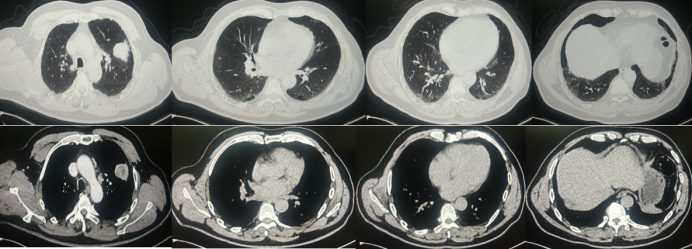

2024年2月,患者无明显诱因出现咳嗽伴痰中带血丝,伴消瘦、乏力、食欲减退,外院予抗炎治疗后症状无改善。胸部CT检查示左肺上叶肿物影、纵隔及左肺门多发肿大淋巴结,双肺胸膜下散在浸润及粟粒样小结节,双下肺肺气肿,左侧肾上腺肿物(图1)

图片

1  患者胸部CT(2024-02-20)

进一步行PET-CT检查提示:左肺上叶前段不规则肿物,考虑周围型肺癌;纵隔内主动脉弓旁及左肺门多发结节,考虑淋巴结转移;左侧肾上腺结节,良性可能性大,不除外转移。